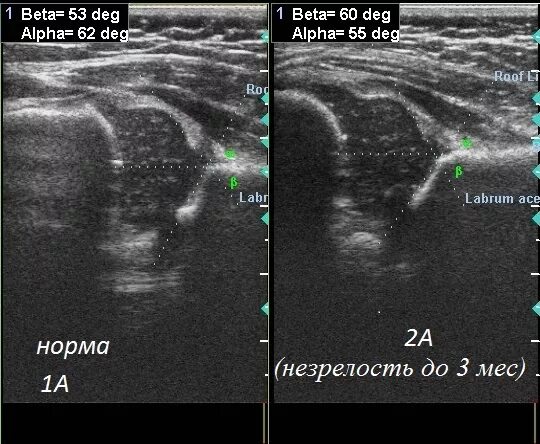

Норма углов тазобедренных